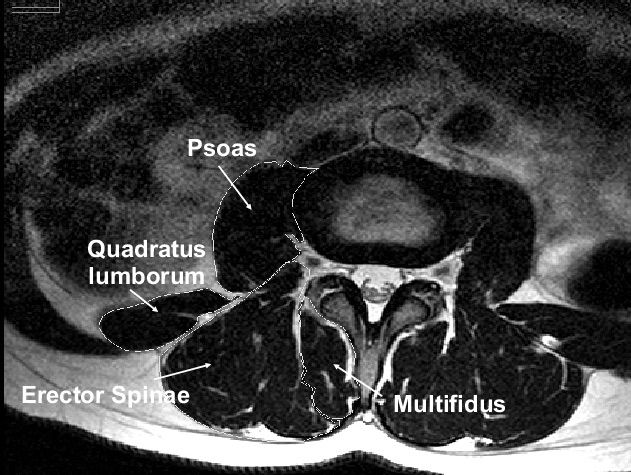

L’IMAT è una di quelle cose che non vengono riportate nel referto della RM, ma offre molte informazioni. Infatti, l’infiltrazione di grasso nel muscolo fa capire che si è in presenza di uno stato infiammatorio, predisponente stati dolorosi, che non dipendono principalmente da una problematica meccanica.

Un muscolo in quello stato sarà meno forte, meno efficiente e più disidratato.

L’IMAT ci dice anche che siamo in una condizione di:

- insulino resistenza,

- scarsa attività fisica,

- stato infiammatorio sistemico di basso grado,

- alimentazione a prevalenza infiammatoria (zuccheri, cibi industriali e processati),

- respirazione poco funzionale (ricordiamoci che il diaframma è un muscolo che lavora in sinergia col pavimento pelvico -altri muscoli - gli psoas, lo stretto toraci superiore),

- stress cronico: rimugini, possibili traumi emotivi ricorrenti, risposte allo stress ora poco funzionali, …

Questo è un esempio che ci fa capire che l’ernia non è la causa del problema, ma una conseguenza di un tessuto muscolare deteriorato (mi perdonino i colleghi per l’estrema semplicità, ma lo scopo è parlare a un pubblico vasto perché si possa diffondere conoscenza)